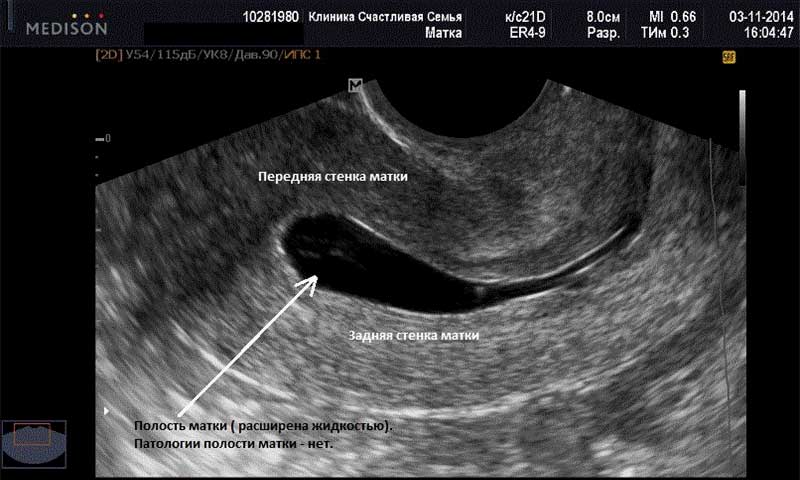

Ультразвуковое исследование плода позволяет определить до 3-х месяцев эмбриональный срок беременности по КТР (расстоянию от копчика к темени эмбриона). Он меньше акушерского на две недели. Врач по результату измерения в таблице находит соответствующий срок.

23ДПП первое УЗИ: 1ПЯ-средний внутренний диаметр-10мм, эмбрион четко не визуализируется, канал шейки матки закрыт, матка в нормотонусе. Заключение:Беременность соответсвует сроку 3 недели 2 дня (от зачатия)

Мое первое УЗИ на 19ДПП. В полости матки визуализируется 1ПЯ, СВД-5,5мм округлой формы. ПЯ и ЛЯ с множеством ж/тел. Диагноз — беременность малого срока. Теперь следующее УЗИ на 34ДПП, 25.08.10. Сказали, что должно сердечко биться на сл.УЗИ.

Привет всем! Опять я вся такая нервная. С начала протокола прошло уже 6 недень. И вот я вся такая еле дотерпевшая прошла УЗИ. И теперь уже 2 дня не сплю. Результат: на 24 ДПП плодное яйцо 13 мм с эмбрионо КТР 3,3 мм (отвечает 5 неделям, желточный мешок 2.6 мм ЧСС 112 уд